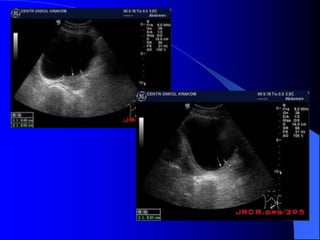

- Siãu ám

Khoï cháøn âoaïn u bãø tháûn, niãûu quaín nãúu

khäng coï æï næåïc âaìi bãø tháûn niãûu quaín.

U baìng quang trãn siãu ám tháúy hçnh tàng

ám trong baìng quang coï næåïc tiãøu räùng ám.

Siãu ám coï thãø tháúy mæïc âäü xám láún thaình

baìng quang vaì ngoaìi thaình baìng quang.